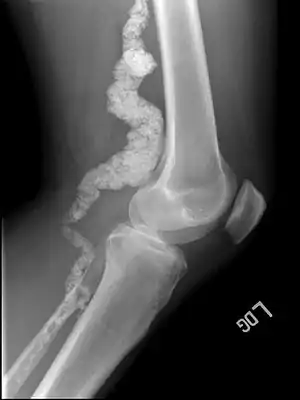

| A knee x-ray of a person with ACDC | |

Arterial calcification due to deficiency of CD73 (ACDC) is a rare genetic disorder that causes calcium buildup in the arteries and joints of the hands and feet, and other areas below the waist.[1] Although patients exhibiting these symptoms have been identified as early as 1914, this disorder had not been studied extensively until recently. The identification of the specific ACDC gene and mutations occurred in 2011. ACDC is caused by a mutation in the NT5E gene, which prevents calcium-removing agents from functioning,.[1][2] Patients with this mutation experience chronic pain, difficulty moving, and increased risk of cardiovascular problems.[1][2] In experiments at the molecular level, treatment with adenosine or a phosphatase inhibitor reversed and prevented calcification, suggesting they could be used as possible treatment methods.[1] There is currently no cure for ACDC, and patients have limited treatment options which focus primarily on removal of blood calcium and improving mobility.[1][2]